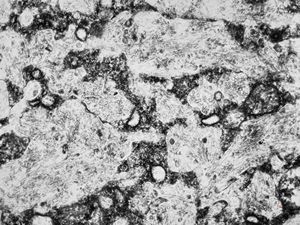

M,58y. | spleen - thesaurismosis of unknown origin … postmedicamentous?